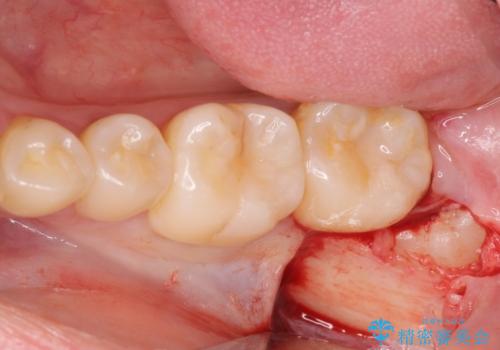

- 左下親知らずが腫れてる感じがして痛いとの事で来院。

抜歯を希望されたので抜歯術を行いました。

親知らずを長年放置すると手前の歯が虫歯になるリスクがあがります。

虫歯になる前に親知らずは抜歯することをお勧めします。